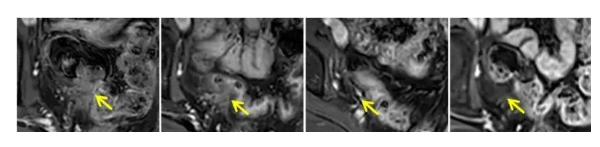

案例2:

另一位晚期子宫内膜癌患者的肿瘤在直肠前壁不断恶化并发生转移,但在采用了TIL治疗后,仅仅10个月的时间,肿瘤就完全消失了,她也因此达到了完全缓解的状态,且这种状态保持了15个月之久。